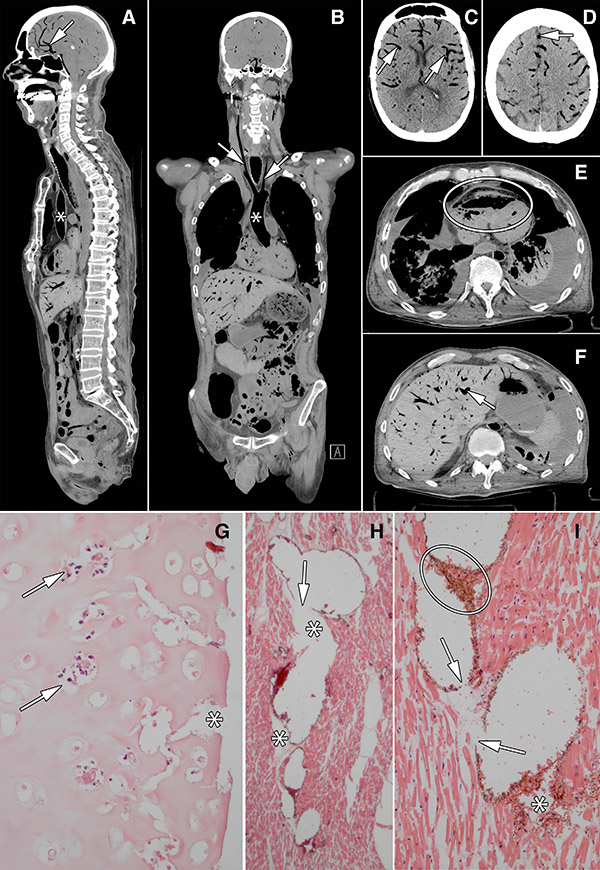

Images in 60-year old man who underwent bilateral lung transplant 2 months before death. Images show aorta (∗ in A and B), carotid arteries (arrows in B), visceral blood vessels (cerebral blood vessels: arrows in A, C, D; liver blood vessel: arrow in F), and right ventricle (oval in E). G, Photomicrograph of luminal side of trachea shows disappearance of mucosa and submucosa; tracheal cartilage is necrotic with empty lacunae, nuclear debris (arrows), and clefts (∗). H, I, Photomicrographs of myocardium show blood vessels inflated by air that pushes erythrocytes to the walls and causes rupture of vessels (arrows), allowing air (∗) and erythrocytes (oval in I) to escape into interstitial space, thereby tearing the tissue.